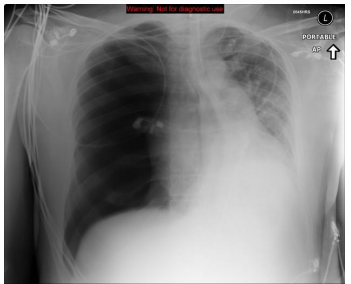

O Rx de tórax faz parte do protocolo inicial do ATLS e o conhecimento dos principais padrões de imagem é obrigatório mesmo para um médico recém-formado que invariavelmente vai se deparar com tal situação no dia a dia de seu ofício.

Um paciente vítima de politrauma é trazido para a sala de emergência com dispnéia, apresentando este Rx de tórax. Qual o principal diagnóstico do exame?